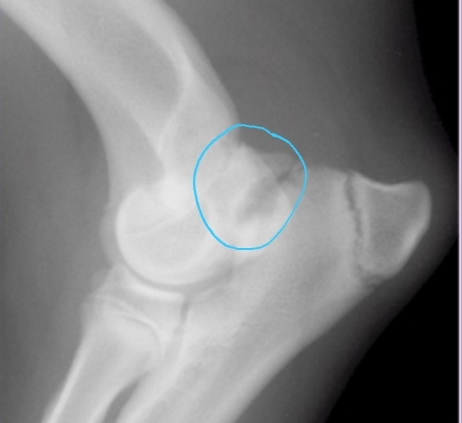

Osteochondrosis and Osteochondritis Dissecans

Et: Defect of normal endochondral ossification

Shoulder

Sig: large breed dogs, rapid growth, 5-10 months

Cs: lameness, pain, decreased ROM, muscle atrophy, effusion

Dt:

Rads: Divot of subchondral bone, OA, free cartilage flap

CT: Detects subtle subchondral bone lesions

Tx: Arthrotomy or arthroscopy

Remove cartilage flap, debride subchondral bone, promote fibrocartilage repair

Osteochondrosis + Osteochondritis Dissecans

Et: Defect in normal endochondral ossification

Shoulder(most common), Elbow, Stifle, Hock

Path: Failure of cartilage to ossify → thickened cartilage (OC) → poor nutrition → mechanical trauma → cartilage fissuring/flap(OCD) → synovial inflammation → pain

Sig: Juvenile large breed dogs

Cs: Lameness, Pain, Decreased ROM, Muscle atrophy, Joint effusion palpable

Dt: Radiographs, CT

Caudal humeral head – lateral view

Tx: Arthrotomy, arthroscopy, remove cartilage flap, debridement of subchondral bleeding bone